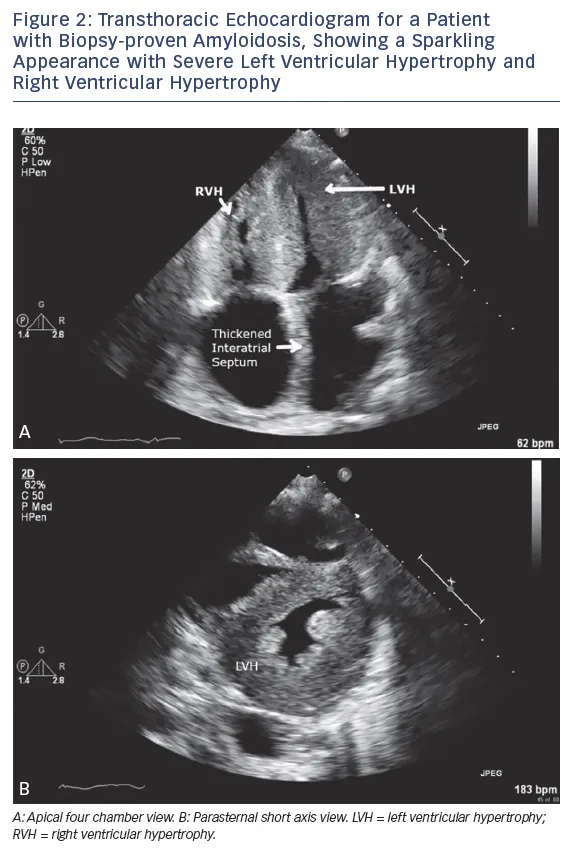

- Dx: Echo (biatrial enlargement, diastolic dysfunction; 'sparkling' myocardium in amyloidosis).

⭐ Amyloidosis is a key cause of RCM, often presenting with a characteristic 'sparkling' appearance on echocardiogram due to amyloid fibril infiltration in the myocardium. Kussmaul's sign is also a classic finding in RCM due to the stiff, non-compliant right ventricle.